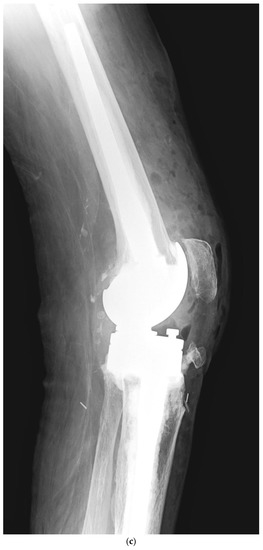

Although one-stage revision TKA is performed in certain situations and centers, a PJI usually requires a two-stage revision TKA, which involves a double surgical intervention. First, the removal of the infected implant (septic loosening) is required. Following this procedure, a period of several weeks of antibiotic treatment is needed until the infection is considered cured (normalization of the ESR and CRP and healing of the surgical wound). The second intervention is the insertion of a new implant, using a model that is stable for proper functioning of the knee [11]. Figure 1 shows a case of PJI (septic loosening) that was solved by a two-stage revision TKA.

Figure 1. (ad). Periprosthetic joint infection of a primary total knee arthroplasty (TKA) that was resolved by a two-stage revision TKA: (a) preoperative anteroposterior (AP) radiograph; (b) preoperative lateral image; (c) postoperative AP radiograph showing the prosthesis implanted in the second-stage revision (rotational hinge design); (d) lateral image of the aforementioned prosthesis.